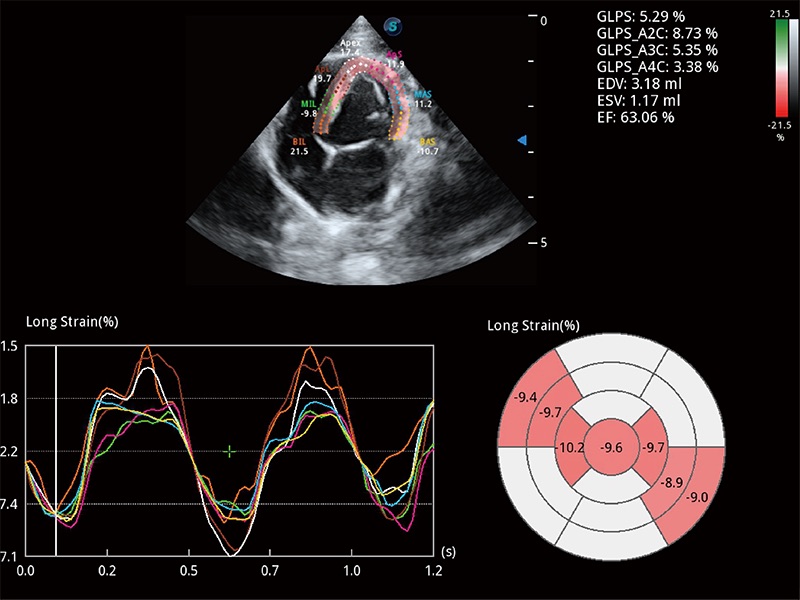

通过心肌识别技术与二维斑点追踪技术相结合,对心脏的超声图像进行量化分析。计算心肌17个节段的应变、应变率、速度、位移等,并通过牛眼图的形式进行呈现。

能够基于左心室壁追踪和辛普森法,自动计算射血分数,支持多个可移动点描迹,与手动测量相比,极大节省了动物医生的时间和精力。

具备多种协议可选,同时支持17阶段划分法和专业的SE报告。